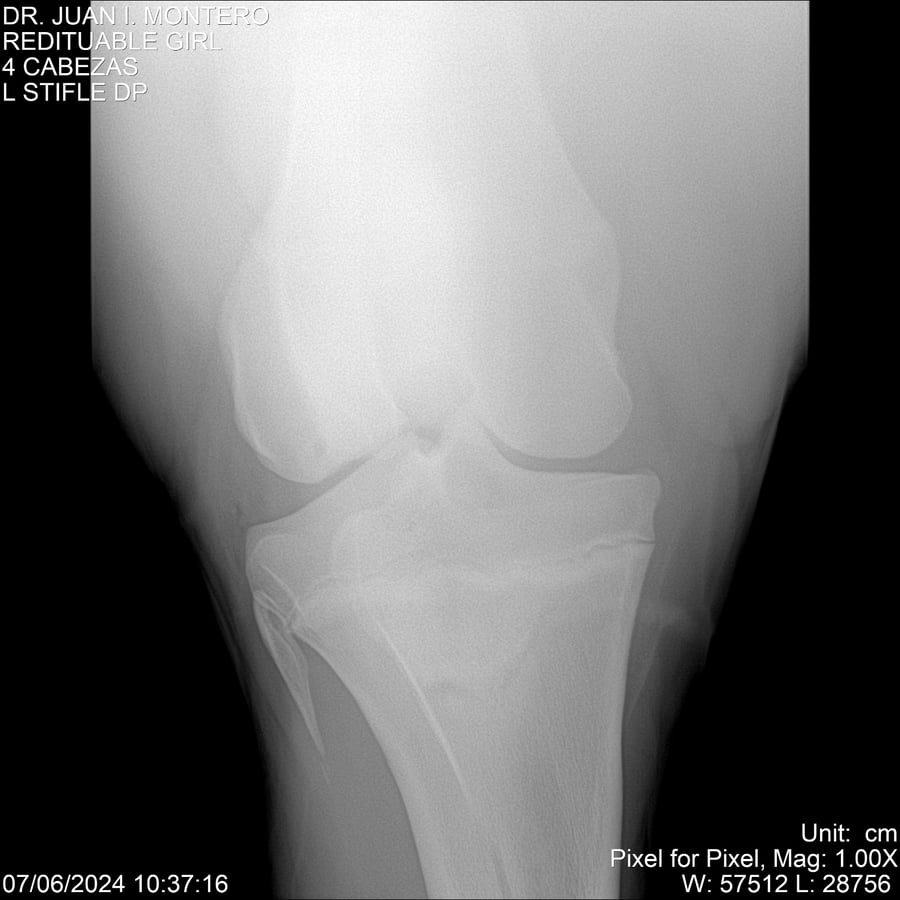

LOTE 19, REDITUABLE GIRL Lote Anterior Volver al remate Lote Siguiente Ficha Contacto Montevideo - Ficha del Lote Identificador: #281096 Categoría: Yeguarizos Montevideo - 79 Visualizaciones ClicData Contacto Empresa: Abelenda N. R., Walter Hugo Nombre*: Teléfono* : E-mail* : Mensaje Enviar Registrese gratis Este contenido Exclusivo está disponible sólo para usuarios registrados Ingresar